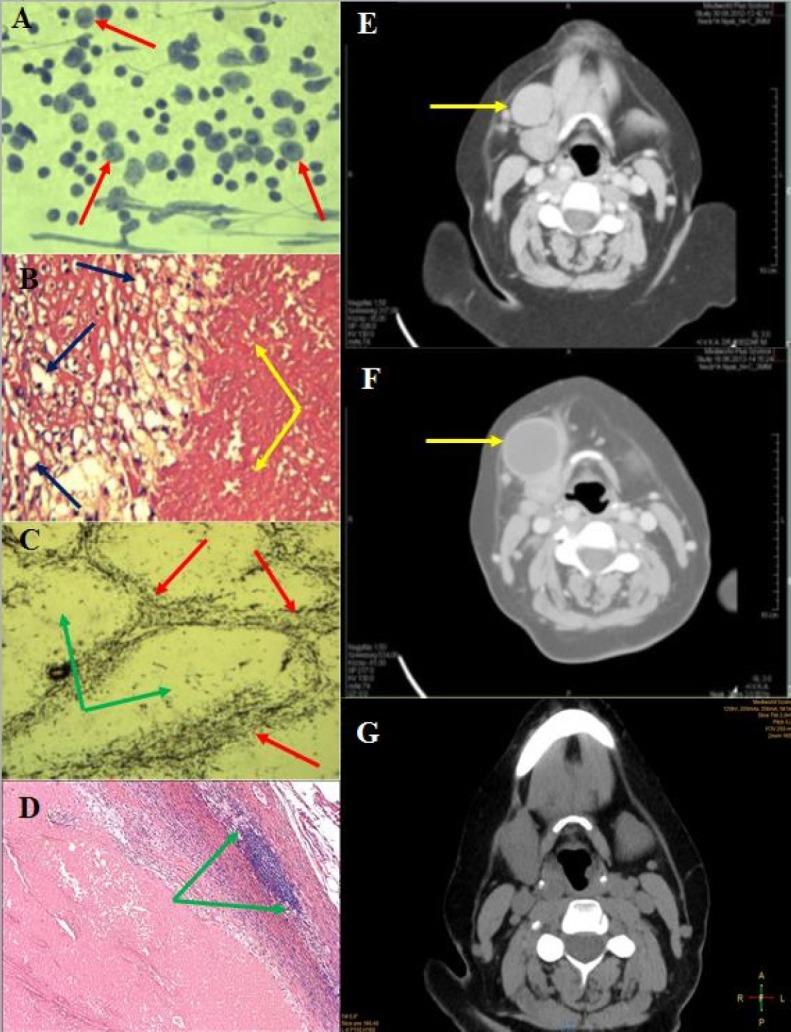

Palpable neck masses are often the only signs of patients visiting their ENT specialists. Lymphadenopathy may be a primary or secondary manifestation of numerous benign and malignant disorders. The medical history, physical examination, imaging and pathological examination may help to set the appropriate diagnosis. Lymph node infarction is a very rare entity among the various pathologies involving the lymph nodes. We hereby present three cases, in which infarction was the only symptom, no associated condition occurred.

可触及的颈部肿块往往是患者就诊于耳鼻喉科专家时的唯一症状。淋巴结病可能是众多良性和恶性疾病的原发性或继发性表现。病史、体格检查、影像学检查和病理检查有助于做出恰当的诊断。在涉及淋巴结的各种病理情况中,淋巴结梗死是一种非常罕见的病症。我们在此呈现三例病例,其中梗死是唯一症状,未出现相关病症。